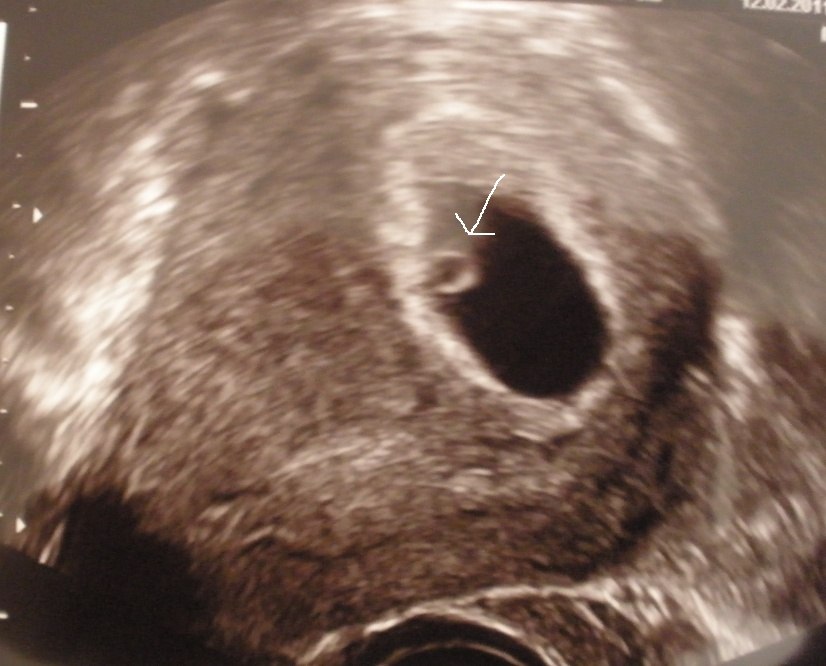

Så har vi været til tryghedsscanning. Det var en rigtig god oplevelse. Skulle scannes indenvendigt, da jeg ikke var længere henne, men det gjorde mig ikke noget. Man kunne tydeligt se det lille hjerte blinke afsted, og jeg blev helt rørt! Alt er som det skal være, og det sidde inde i livmoderen og ikke udenfor som jeg også havde frygtet. Vi har fået både billeder og DVD med

Hun sagde dog, at hun ikke mente jeg var 7+0, hvilket jeg er enig i, da jeg ikke kunne teste positiv på 28. dagen. Hun sagde at hun mente jeg var 6+et eller andet, men hun vidste ikke præcis hvor meget. Det kunne hun se dels ud fra størrelsen, og også fordi at de små fosteres hjerter normalt blinker hurtigere end vi andres, men i starten blinker de i samme hastighed som vores, og det var dén hastighed det lille foster blinkede med. Ergo mente hun, at hjertet ikke havde banket så længe.

Hun sagde at hun mente jeg kunne være alt imellem 5+6 og 6+3 eller 4. Det var svært at sige præcist. Jeg ved jeg er mindst 6+0 grundet testtidspunktet, og mit eget bud er 6+2 eller 3, men det må jeg jo finde præcist ud af til nakkefolds